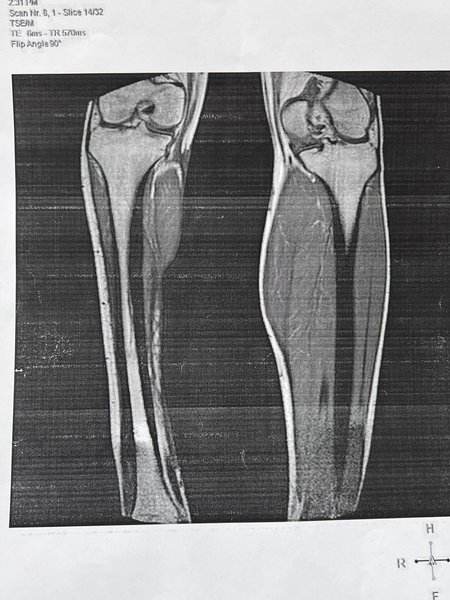

21-летний защитник получил тяжелое ранение ноги во время обороны Харькова и перенес 15 операций. На скандал уже отреагировал Минздрав.

В Харькове руководительница областной медико-социальной экспертной комиссии отказала бойцу Сил обороны, который получил ранения во время боев за Харьков и перенес уже 15 операций, в изменении группы инвалидности. Она дала ему "совет" — отрезать ногу и получить 2 группу инвалидности. Об этом украинский защитник Дмитрий Олейник рассказал в сети.

По словам защитника, он пришел на МСЭК для установления изменения группы инвалидности, поскольку его нога "окончательно потеряла функциональность". Руководительница комиссии Лариса Б. ему сказала: "Так зачем ты оставлял свою ногу надо было чтобы ее отрезали и была бы 2 группа". Эти слова возмутили защитника.

"Это так выглядит благодарность людям, которые стали на защиту государства. Так тогда получается надо было и погибнуть в одном из штурмов. Это как надо относиться к военным, что можно не принимать во внимание выводы киевских клиник о том, что правая нога потеряла свою функциональную способность и является биопротезом. Этого комиссии МСЭК мало", — рассказал Дмитрий.

По словам Дмитрия, его собрат имеет аналогичное заключение и выводы почти одинаковые, а в его случае это статья 61А, которая включает в себя еще больший перечень повреждений чем статья 62А, которая у его собрата.